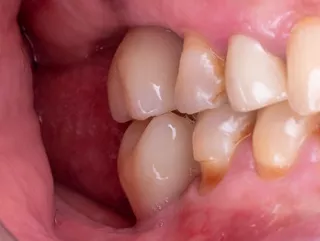

1. Pre-operative clinical view

The occlusal view shows a ridge with a satisfactory width and a thick, healthy periodontal phenotype.